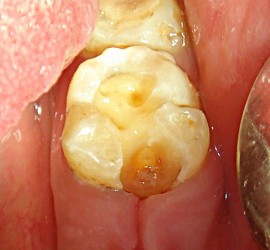

Аномалии строения и пороки развития зубов Пороки тканей зуба многообразны, они могут проявляться изолированно и сочетаться с аномалиями строения и пороками развития органов и систем всего детского организма, в том числе челюстно-лицевой области. Ткани зуба имеют эктодермальное (эмаль) и мезодермальное (дентин, пульпа, цемент) происхождение. В связи с этим пороки эмали […]